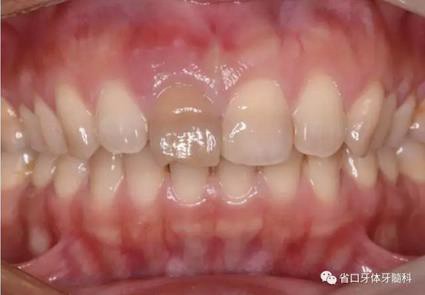

1.?病例簡(jiǎn)介 43歲女性患者,主拆:右上前牙松動(dòng)不適數(shù)日要求修復(fù)。現(xiàn)病史:患者數(shù)年前右上前牙因“齲壞”于外院行根管治療(具體不詳),數(shù)日前牙冠松動(dòng)不適,現(xiàn)覺(jué)影響咀嚼及美觀,遂來(lái)我院要求進(jìn)一步診治。否認(rèn)高血壓、心臟病等重大疾病,否認(rèn)結(jié)核、肝炎等傳染病史,否認(rèn)手 術(shù)、輸血史等,未發(fā)現(xiàn)藥物過(guò)敏。無(wú)吸煙習(xí)慣。臨床檢查:口外觀顏面基 本對(duì)稱,皮膚無(wú)紅腫破潰,顳下頜關(guān)節(jié)區(qū)無(wú)彈響、雜音、壓痛,開(kāi)口度約 37mm,開(kāi)口型“↓”,頜下、刻下和頸部未及腫大淋巴結(jié)。中位笑線??趦?nèi)檢查,口腔衛(wèi)生可,色素(+),BOP(-),PD=2mm,上頜右側(cè)中切 牙冠部變色,冠根折斷至齦下3mm,叩不適,松動(dòng)Ⅱ°~Ⅲ°。牙齦稍紅, 齦緣水平及齦乳頭高度可,屬于中厚齦生物型,附著齦寬度約5mm,唇系帶附著可。上頜右側(cè)中切牙缺牙間隙與對(duì)側(cè)同名牙一致,約>7mm,修復(fù)空 間良好。與對(duì)頜牙覆合覆蓋正常。MCT檢查示上頜右側(cè)中切牙冠根折斷至骨 下,根管內(nèi)見(jiàn)充填物,根充不全,根尖見(jiàn)陰影,大小約3mm×3mm。牙槽窩根方可用骨量可,唇側(cè)骨壁完整,冠方骨壁厚度約1mm。

圖3 術(shù)前口內(nèi)照